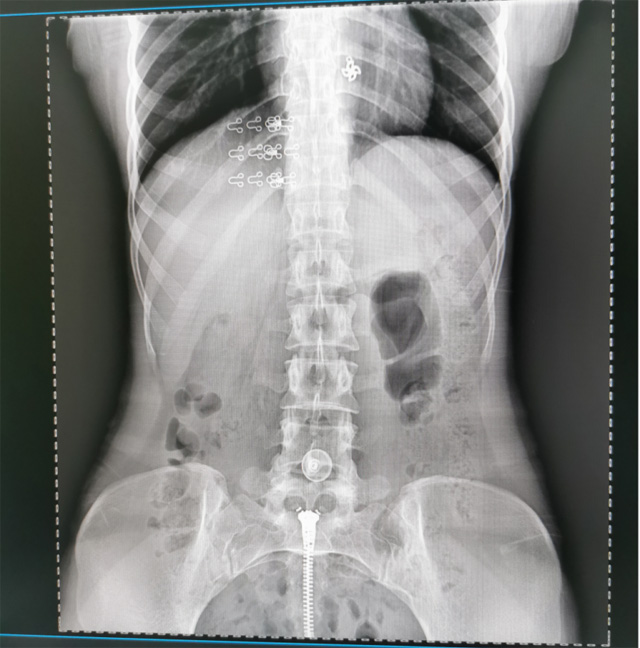

提高醫(yī)院的影像科的醫(yī)療服務水平,滿足滿足人民群眾不斷增長的醫(yī)療需求,促進醫(yī)療技術快速發(fā)展。醫(yī)院都引進懸吊DR拍片設備新一代數(shù)字化X線攝影系統(tǒng)。標志著醫(yī)院的診療水平又上升一個新的臺階。懸吊DR滿足人體頭部、胸部、腹部、腰椎、四肢等部位的數(shù)字攝影檢查,可以檢查呼吸系統(tǒng)疾病,心臟系統(tǒng)的疾病、骨關節(jié)系統(tǒng)的疾病,子宮輸卵管造影、胃腸道造影,.有職業(yè)病體檢篩查塵肺病功能。通過DR數(shù)字化攝影,分段連續(xù)、重疊采集數(shù)字化圖像,利用軟件對圖像進行拼接的方式來獲得全脊柱、全上肢或全下肢的圖像。新設備的圖像更清晰,臨床拍攝避免患者再次搬運和移動產(chǎn)生的痛苦,是創(chuàng)傷骨折患者的福音。輻射減少受照劑量50%,后處理能力強、圖像質量高。有效降低操作難度,縮短工作流程,尤其適合大批量體檢。

具有射線劑量小、圖像清晰度高、誤差小等特點,懸吊DR已廣泛應用于各級醫(yī)療機構的體檢中心,越來越受到臨床醫(yī)生的肯定和患者的青睞。為臨床診斷工作提供更加直觀有效的技術支持,大大提高了患者就醫(yī)效率從而為患者提供更加優(yōu)質的醫(yī)療服務。提高了其成像質量和臨床應用價值,并極大減少了受照輻射劑量。有效滿足了各種常見疾病的臨床診斷和治療需求。以醫(yī)療質量為根本,以優(yōu)質服務為導向,竭誠為人民群眾的健康保駕護航。